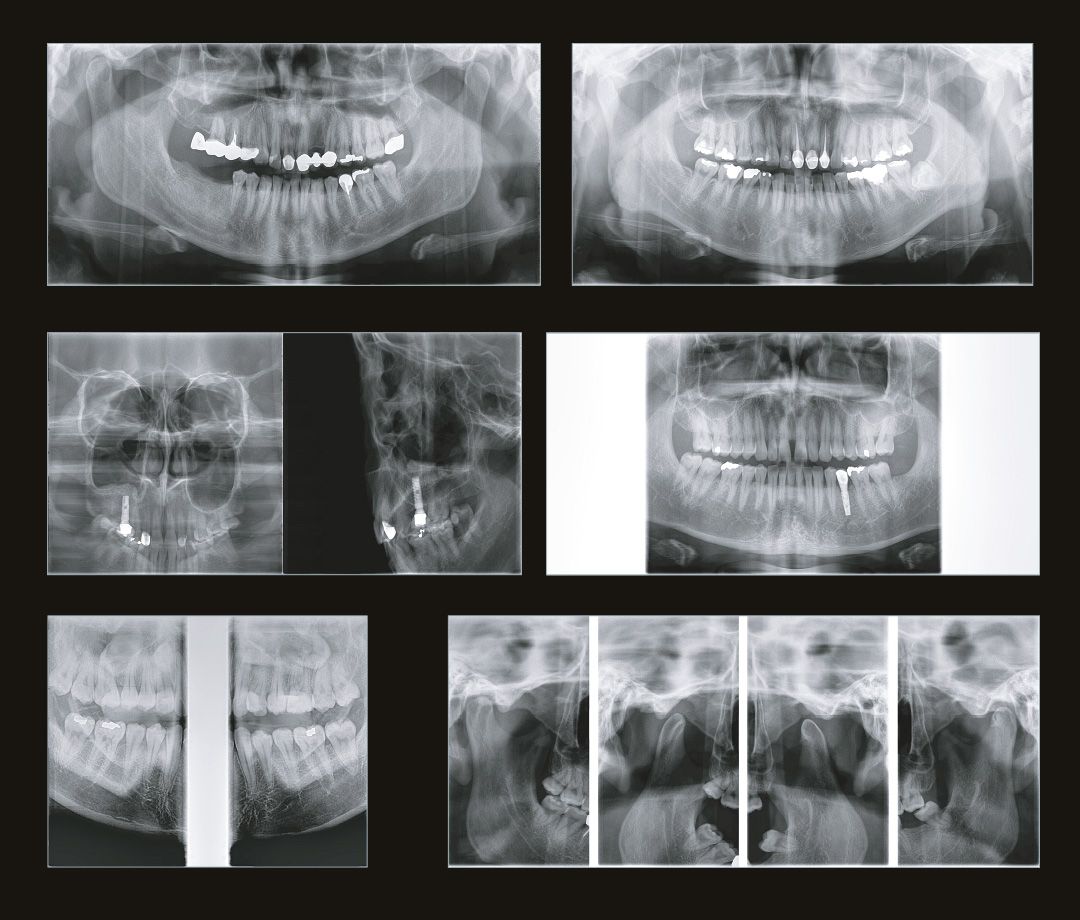

Современная стоматология уже давно не работает вслепую, и каждому из направлений стоматологии необходимо проводить рентгеновские исследования:

• Стоматолог-терапевт по снимку видит не только кариес, а также способен оценить, как периодонтальные ткани, так и различные воспалительные процессы затрагивающие пульпарную камеру.

• Стоматолог-хирург не способен производить свои манипуляции без снимка КТ, иначе он будет вынужден действовать вслепую, не сумев оценить анатомию области вмешательства.

• Стоматолог-ортопед не сможет гарантировать надежность конструкции без правильной оценки стабильности опорных зубов при помощи снимка КТ.

• Стоматологу-ортодонту, чтобы правильно простроить план лечения, помимо слепков, так же нужен снимок КТ.